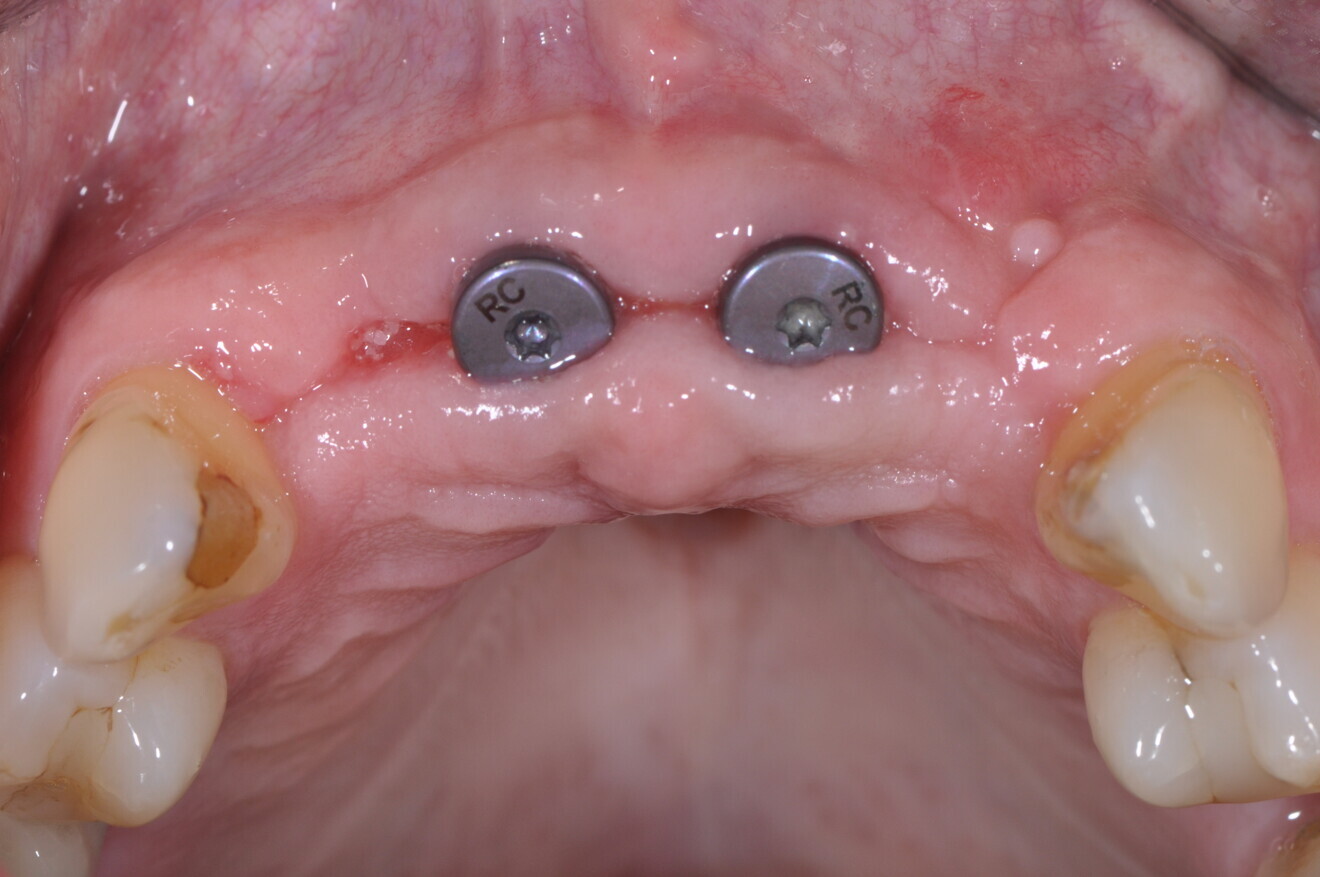

After completion of the planning and drilling reconstruction, the surgical guide was 3D-printed with a Stratasys printer using MED610 resin (Stratasys). The two implants (4.1 × 12.0 mm Straumann Bone Level Tapered, Regular CrossFit, SLActive, Roxolid) were then placed utilising the Straumann guided surgery kit for precise guidance. The remaining piece of amalgam in the bone of tooth #21 was carefully removed—only a small piece in the gingiva remained (Fig. 12). The buccal bone was again thickened with EthOss, and the wound was closed with a semi-submerged technique, facilitating proper healing and integration of the implants (Figs. 13a & b).

Figs. 13a & b: Intra-oral view of the implants with healing abutments after placement